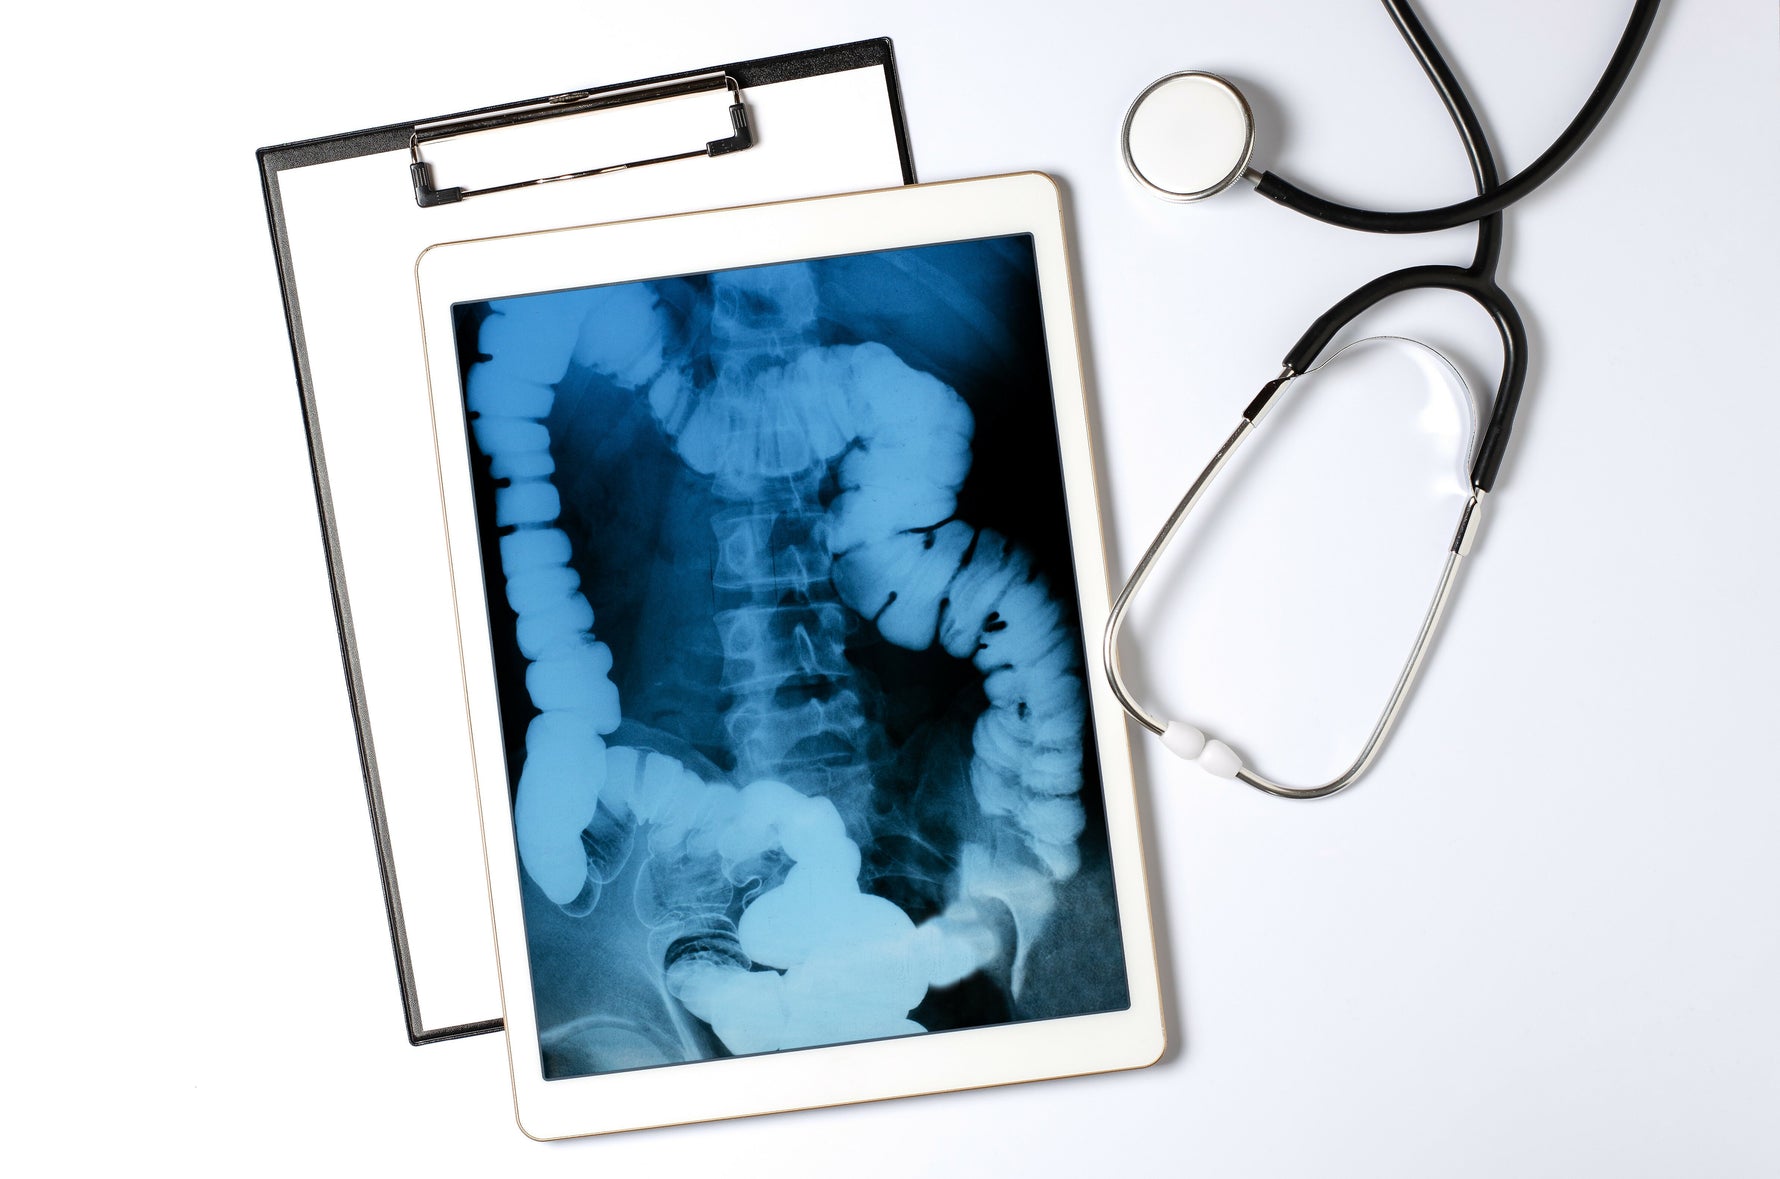

Ever wondered what lies beneath your skin? X-rays can reveal just that. During an X-ray examination, a specially trained medical professional can see exactly what your bone structure looks like and interpret what this imaging reveals. The discovery of X-rays by Wilhelm Conrad Röntgen in 1895 was a milestone that satisfied the prevailing curiosity about the interior of the human body – it allows us to literally look beneath the skin. This article by Animus Medicus brings you closer to the world of X-rays and explains what to expect during an X-ray examination. This way, you can approach your next X-ray examination with ease and learn some fascinating things about X-ray technology. What are X-rays? X-rays are a form of electromagnetic radiation, similar to the light we see or the radio waves that transmit music and news. The difference lies in their wavelength: X-rays are much shorter, which gives them the ability to penetrate certain materials, such as our bodies. X-rays were discovered accidentally by the physicist Wilhelm Conrad Röntgen, who noticed a mysterious radiation that darkened photographic plates while experimenting with cathode ray tubes. Röntgen's discovery revolutionized physics on one hand and became an indispensable tool in medical diagnostics on the other. How an X-ray machine works The function of an X-ray machine is to create an image of something that lies beneath an opaque surface. In a classic medical X-ray machine, it essentially involves a tube that shoots electrons at a piece of metal. When the electrons hit, X-rays are produced and passed through the body being examined. Since different materials absorb the rays differently, an image is created on a detector or photographic plate. Bones appear white, soft tissues in shades of gray, and air appears black. Nowadays, digital X-ray techniques can directly convert these rays into images displayed on a screen. This modernization allows for immediate assessment of the imaging by the medical professional. X-ray explained: The procedure For those who have never experienced an X-ray examination, it might be hard to imagine. Here’s how an X-ray examination typically proceeds: Preparation: When it's your turn for the X-ray, you are often first taken to a regular treatment room before entering the room with the X-ray machine. The X-ray procedure is often briefly explained to you. You may be asked to remove certain clothing items, such as medical socks for foot injuries, and change into a gown. Personal items like anatomical jewelry and piercings should also be removed before the X-ray. Safety Measures: Although X-rays in high doses can be harmful, the amounts used in a typical X-ray examination are very low. Nevertheless, lead aprons or other protective measures are used to shield body parts that are not being examined. The X-ray: An X-ray is quick and painless. You will be asked to stand or lie still while the X-ray machine is briefly activated. Your position depends on the body part being imaged. The medical staff will help you position yourself to obtain the best possible image. It is crucial to stay still during the brief moment the image is taken to ensure clarity. After the X-ray: Once the images are taken, you can get dressed and leave the room. The entire procedure often takes only a few minutes, and the results are evaluated by a radiologist, who discusses the findings with you and your treating physician. Understanding anatomy through X-rays of bones What’s remarkable about X-rays is how they reveal the hidden structures of our bodies. They enable doctors to diagnose fractures, locate foreign objects, or assess the health of joints. X-rays are not limited to the human body; they also provide insights into the anatomy of animals, which is essential for veterinary diagnoses. X-ray imaging fascinates not only medical professionals but also the general public, as it makes visible what is invisible to the naked eye. The importance of X-rays for diagnosis X-rays are often the first step in the diagnostic process. Without them, a fracture might only be guessed. The anatomical images from an X-ray can reveal conditions that are not detectable through external examination methods. These include the presence of tumors, the extent of an infection, the presence of a bone injury, or the stage of a disease. Interpreting X-ray images requires expertise, as anomalies in bones and other parts of the human anatomy are not always easy to recognize and interpret. Your specialist will explain your X-ray results in detail and recommend further treatment. X-rays beyond medicine The application of X-rays is not limited to the medical field. Here are some other fascinating areas where X-rays are used: Art and Archaeology: Analysis of artworks and archaeological finds, revealing hidden layers and previous modifications, and estimating the age of bones based on their condition. Industry: Examination of material structures and detection of flaws. X-rays can identify cracks or air pockets, allowing for the sorting out of defective materials. Security Technology: Detection and prevention of hazards, such as at airports. Objects and clothing are scanned for dangerous items. Other Fields: Geology, astronomy, and many other areas also benefit from X-ray technology. The indispensable technology of X-rays X-ray machines and their function allow us to gain deep insights into the world around us and within us. This technology has revolutionized medical diagnostics and finds applications in many other areas. Interested in anatomy and medicine? Did you enjoy this article and are interested in anatomy and medicine? Then perhaps our anatomy phone cases or anatomy pins from Animus Medicus are something for you. Visit our shop and discover our unique products!